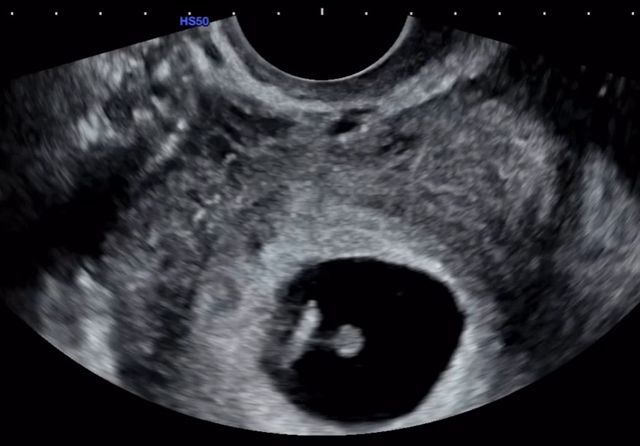

이날 16기 옥순은 초음파 사진도 함께 공개하며 "정말 감사하게도, 저를 있는 그대로 온전히 사랑해 주는 사람을 만나게 되었다"며 남자친구를 언급, "많은 분들이 임신을 위해 많은 노력을 하고 계신 걸 알기에, 그저 축하만 받기보다 제가 임신을 준비하며 지켜온 작은 습관들과 마음가짐을 함께 나누고 싶다"고 전했다.

사진=16기 옥순 계정